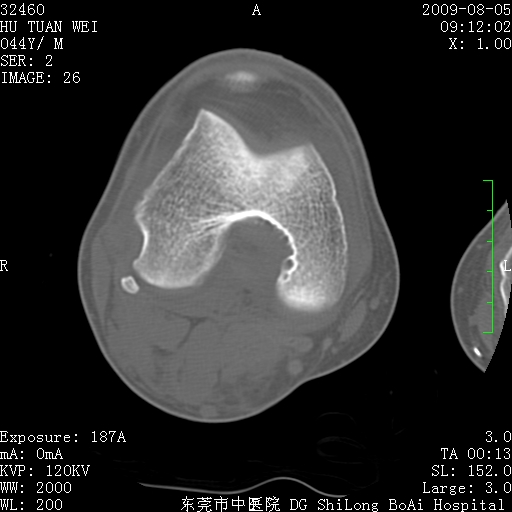

中年男性,膝韧带损伤术前检查!其他病史不清粗,不是我接手病人、且出院了!

1、股骨下段囊状膨胀性病变,边缘硬化明显,内多个残留骨棘呈多房型改变,囊腔密度较高无钙化,膝关节滑膜囊增厚,密度增高,关节腔少量积液。考虑:邻关节囊肿、退变性囊肿(软骨下囊肿)、着色性绒毛结节性滑膜炎、abc、骨巨、良性纤维组织细胞瘤等鉴。虽然年龄偏大,部位于骨端,但有外伤史,本人还是倾向于动脉瘤样骨囊肿(abc)可能性大。邻关节囊肿及软骨下囊肿次之考虑。

2、胫骨髁间棘撕脱骨折,交叉韧带损伤可能;

3、关节退行性改变。

病理结果:色素沉着绒毛结节性滑膜炎

感谢反馈病理结果!本病为慢性关节病变。以关节滑膜高度增生、绒毛结节形成伴含铁血黄素趁着为特点。病因:有炎症、肿瘤、外伤关节出血、代谢障碍、变态反应及感染等学说。增强扫描呈关节腔内单个或多个强化的软组织结节影或滑膜不规则增厚伴关节积液为本病的特征性表现。